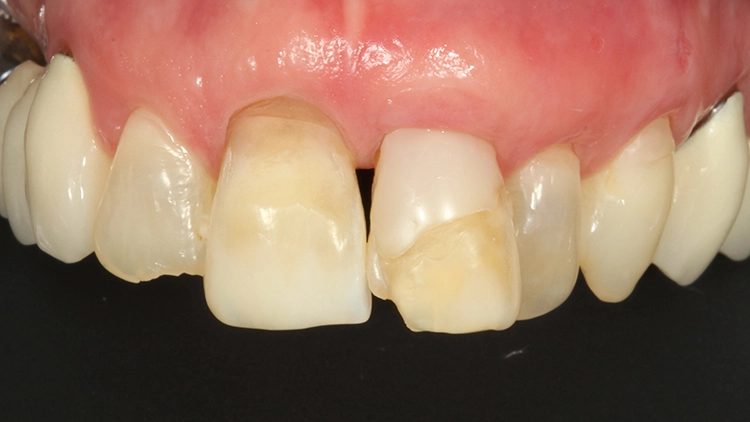

Bei der 61-jährigen Patientin imponierten unterschiedlichste Befunde, die ein ästhetisches Gesamterscheinungsbild gerade der Oberkieferschneidezähne deutlich beeinträchtigten (Ausgangsbefund Bild oben): Labiale und inzisale Zahnhartsubstanzdefekte unterschiedlichster Ausprägung an allen Inzisivi, Verfärbungen der Zähne, eine Fehlstellung sowie multiple Rezessionen und keilförmige Zahnhalsdefekte, die zum Teil von diversen Vorbehandlern mit Zahnhalsfüllungen versorgt worden waren. Es zeigte sich ein Gewebeüberschuss in regio 22, der zumindest teilweise durch die Elongation und Retrusion des Zahnes 22 bedingt zu sein schien. Diese Kombination führte zu einem disharmonischen Gingivaverlauf im Ober- und im Unterkiefer.

Der Wunsch der Patientin zur ästhetischen Neuversorgung bezog sich primär auf die Oberkieferfront. Dabei kam eine kieferorthopädische Therapie für sie nicht infrage. Fokus in der Beratung lag auf der mukogingivalen Grenzlinie: Vollkeramische Restaurationen können zwar auch bei Befunden wie dem vorliegenden eingesetzt werden, das ästhetische Gesamtbild ist dann jedoch ziemlich eingeschränkt, wenn eine derartige Asymmetrie der Gingivaverläufe der einzelnen Zähne besteht.

Die Patientin wurde eingehend über die Möglichkeiten und das operative Vorgehen der präprothetischen Mukogingivalchirurgie aufgeklärt: Die „Zahnfleischästhetik“ kann durch einen Rückgang, auch aber durch einen Überschuss von Gewebe negativ beeinflusst werden. Korrekturen von diesen Missverhältnissen können demnach durch unterschiedliche chirurgische Maßnahmen vorgenommen werden. Aufgrund von Statur und Gesichtsform der Patientin erschienen die Zähne 13 bis 11 nicht zu lang, weshalb gemeinsam mit der Patientin lediglich eine Korrektur des Gingivaverlaufes im 2. Quadranten eingeplant wurde.

So sollte an den Zähnen 21 und 23 eine Rezessionsdeckung mit Verdickung des Gewebes und an Zahn 22 eine chirurgische Kronenverlängerung durch Exzision der Gingiva ohne Osteotomie erfolgen (Low-Crest-Typ). Der Verlauf der Schneidekantenlängen und die Zahnstellung sollten in einem 2. Schritt durch Vollkeramikteilkronen bzw. Veneers mit Inzisalfassung harmonisiert werden. In der Behandlungsplanung dieses Falles kam erschwerend hinzu, dass 3 verschiedene parodontalchirurgische Behandlungsindikationen zusammenkamen: